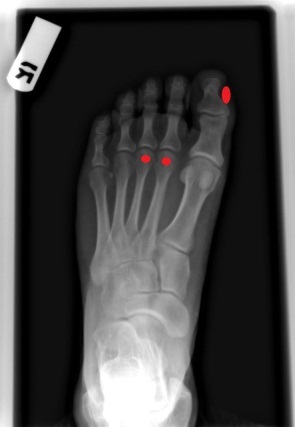

무지외반증은 엄지발가락의 중족지절관절에서 발가락이 바깥쪽(새끼발가락 방향)으로 휘어지는 상태를 말합니다.

엄지발가락이 점점 다른 발가락 쪽으로 기울어지면서 발 앞부분이 넓어지고 뼈가 튀어나오는 형태로 나타납니다.

엄지발가락과 두 번째, 세 번째 발가락의 발등 부위에 굳은살이 있다면 무지외반증을 의심해 볼 수 있습니다.

무지외반증으로 인해 발의 체중 분포가 바뀌면서 특정 부위에 과도한 압력이 가해집니다.

특히 엄지발가락이 제 기능을 못하게 되면 무의식적으로 둘째 발가락에 더 많은 힘을 주게 되어, 이 부위에 굳은살이 생기게 됩니다.